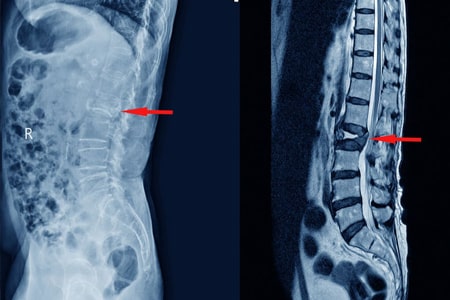

Señales de alerta para descartar fracturas vertebrales en pacientes con dolor lumbar

La evidencia disponible no apoya el uso de muchas señales de alerta para descartar específicamente fracturas vertebrales en pacientes con dolor lumbar (DL). Sobre la base de la evidencia de estudios individuales, pocas señales de alerta individuales parecen informativas debido a que la mayoría tienen una exactitud diagnóstica deficiente según lo indican los cálculos imprecisos de los cocientes de probabilidad. Cuando se usaron combinaciones de señales de alerta el rendimiento pareció mejorar. Cochrane Database Syst Rev. 28 de noviembre de 2023